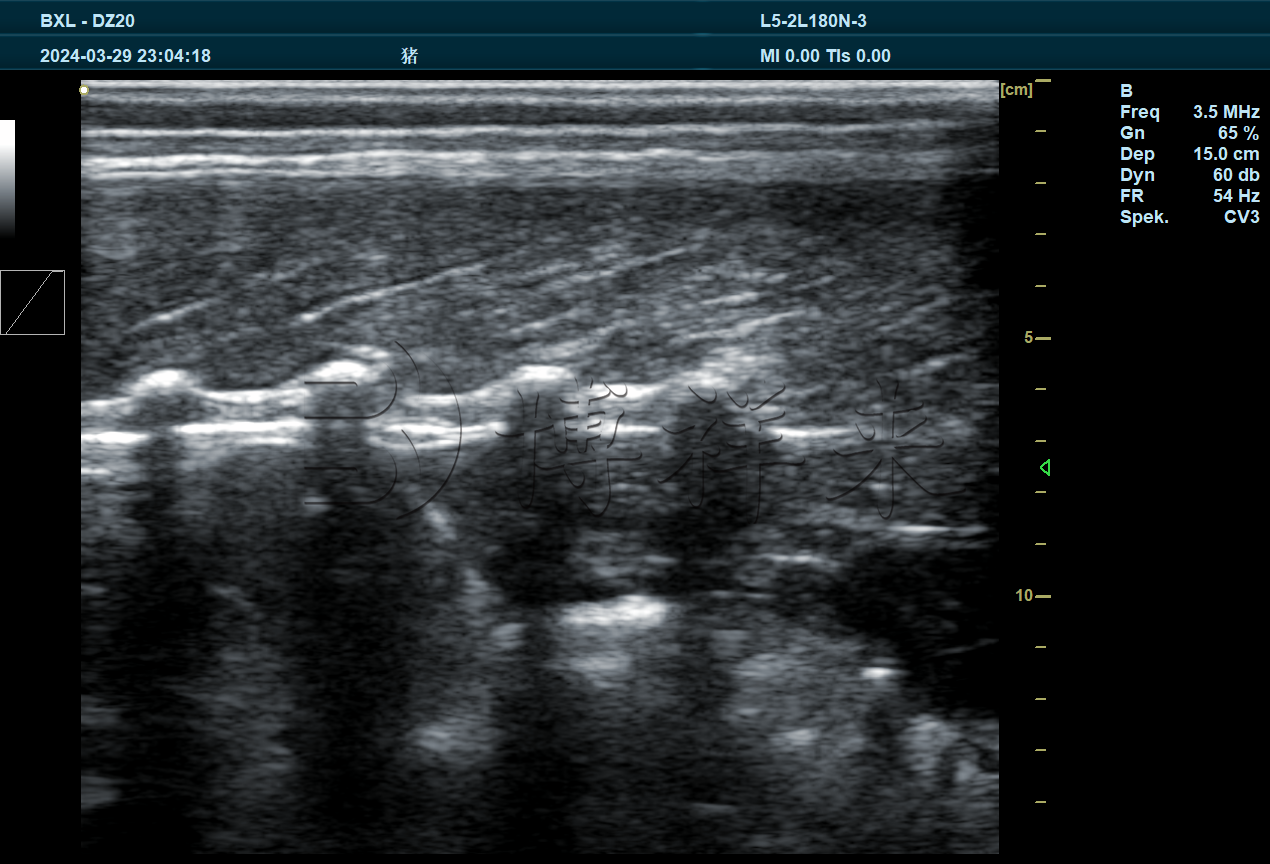

BXL-DZ20是一款多功能兽用全数字彩色多普勒B超仪,可以适配多种探头进行不同超声检测,包括猪牛羊妊娠检测,胎儿发育情况,卵泡黄体发育情况,死活胎,多胎检测,马肌腱韧带检测,背膘眼肌检测等。

4.1、BXL3.5L15A,16cm背膘眼肌专用探头

实拍图片

图像特点